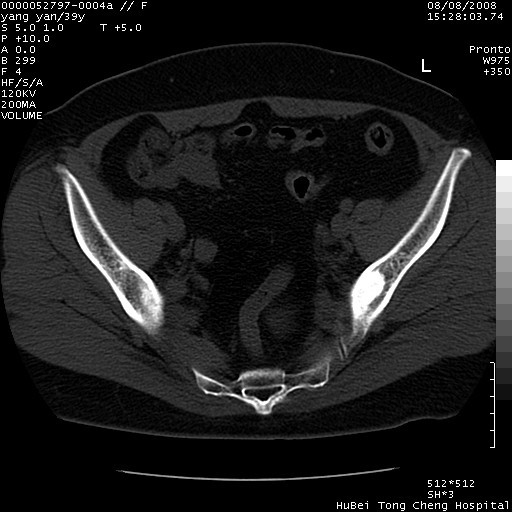

患者 女,39岁。因外伤检查,偶然发现。

典型!双侧骶髂关节致密性骨炎。

病变累及髂骨关节面,腰椎椎小关节结构紊乱,不除外强直性脊柱炎,建议结合实验室检查

典型!病变主要累及双侧髂骨。常见于育龄期妇女。

致密性骨炎,一般不跨越关节面,可是这个骶骨关节面也有硬化。

髂骨致密性骨炎系一种以骨质硬化为特点的非特异性炎症,有高度致密的骨硬化现象,尤其以髂骨下2/3更为明显,但关节间隙则无改变。因位于骶髂关节,且该关节症状明显,故又称之为“骶髂关节致密性骨炎”。 本病90%以上为中年女性,以妊娠后期、尤其分娩后为多见,亦可见于尿路或女性附件慢性感染后,或盆腔内其他感染。此外,臀骶部的外伤亦可诱发或引起本病。  妊娠、分娩及外伤均可引起骶髂关节韧带的撕裂而易使局部的血供受阻。因此早期局部呈现充血、水肿及渗出增加等,渐而局部出现增生与变性反应,随着胶原纤维的致密化而向硬化演变;血管形成厚壁血管,易闭塞而引起髂骨耳状面处缺血和缺氧,骨质呈现硬化性改变,以致手术时局部出血较少。骶髂关节囊壁显示纤维增生、弹性降低及松动样改变。继发于盆腔内炎症者亦出现相类似的病理改变,可能系细菌内毒素作用所致。